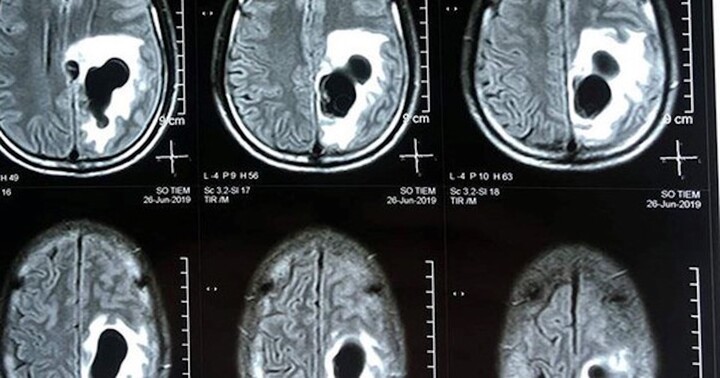

Đau đầu ngày càng tăng về cường độ, người đàn ông đi khám tâm thần, uống thuốc nhưng không khỏi, hóa ra anh bị sán làm tổ trong não.